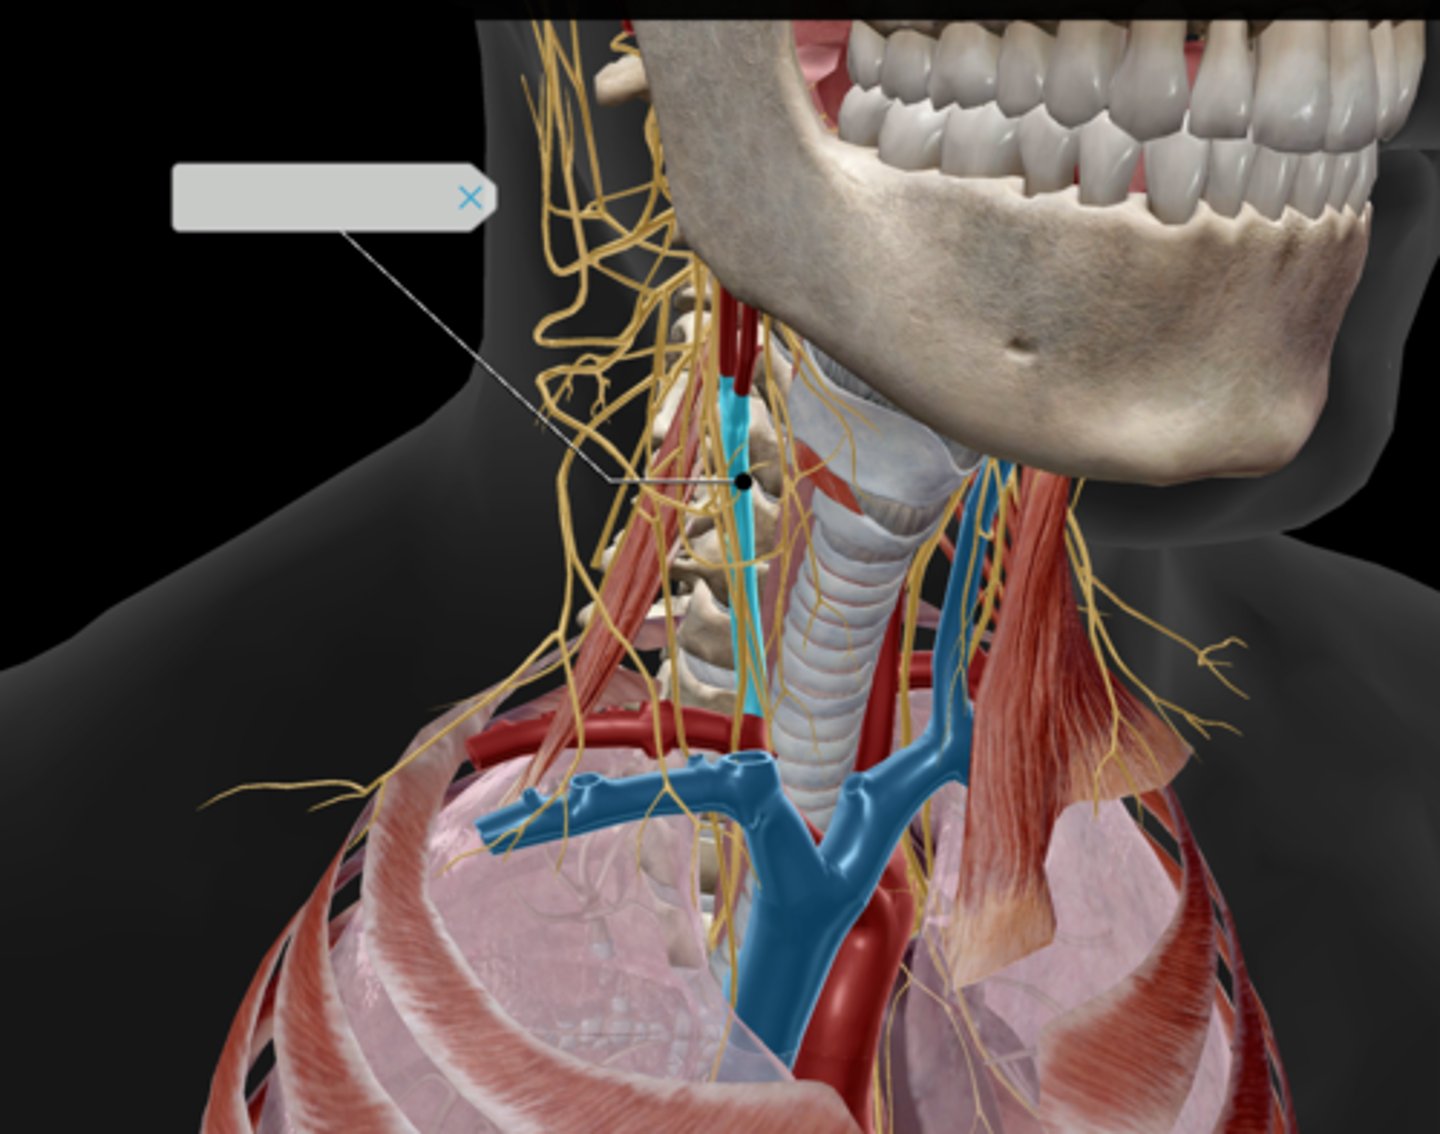

Cisterna chyli

Thoracic duct (left lymphatic duct)

Subclavian trunk

Subclavian vein

Internal jugular vein

Vagus nerve (CN X)